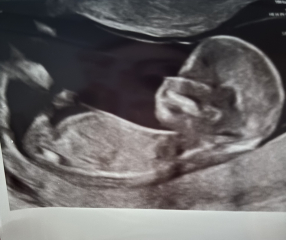

Lunamoon23 · 14/06/2024 18:49

Had my first scan today! Everything looks perfect thank god! I'm further along than expected at 13 weeks + 4! Was a very active little bean! Thought I'd share my scan photos to see if anyone has any nub theorys??

Boy / Girl?

littlepanda88 · 14/06/2024 19:08

@Lunamoon23 aww what a lovely scan!! Going by the nub I'd say boy!! :-) during my scan baby was so wriggly, it was hard to get decent shots! :)

Hahaha EVERYONE so far has said boy, I think the same, my husband is one of 4. 3 boys, 1 girl.